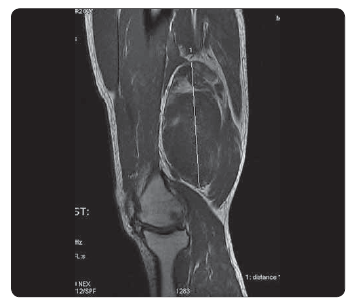

Myxoidni Liposarkom Stehna Linkos Cz